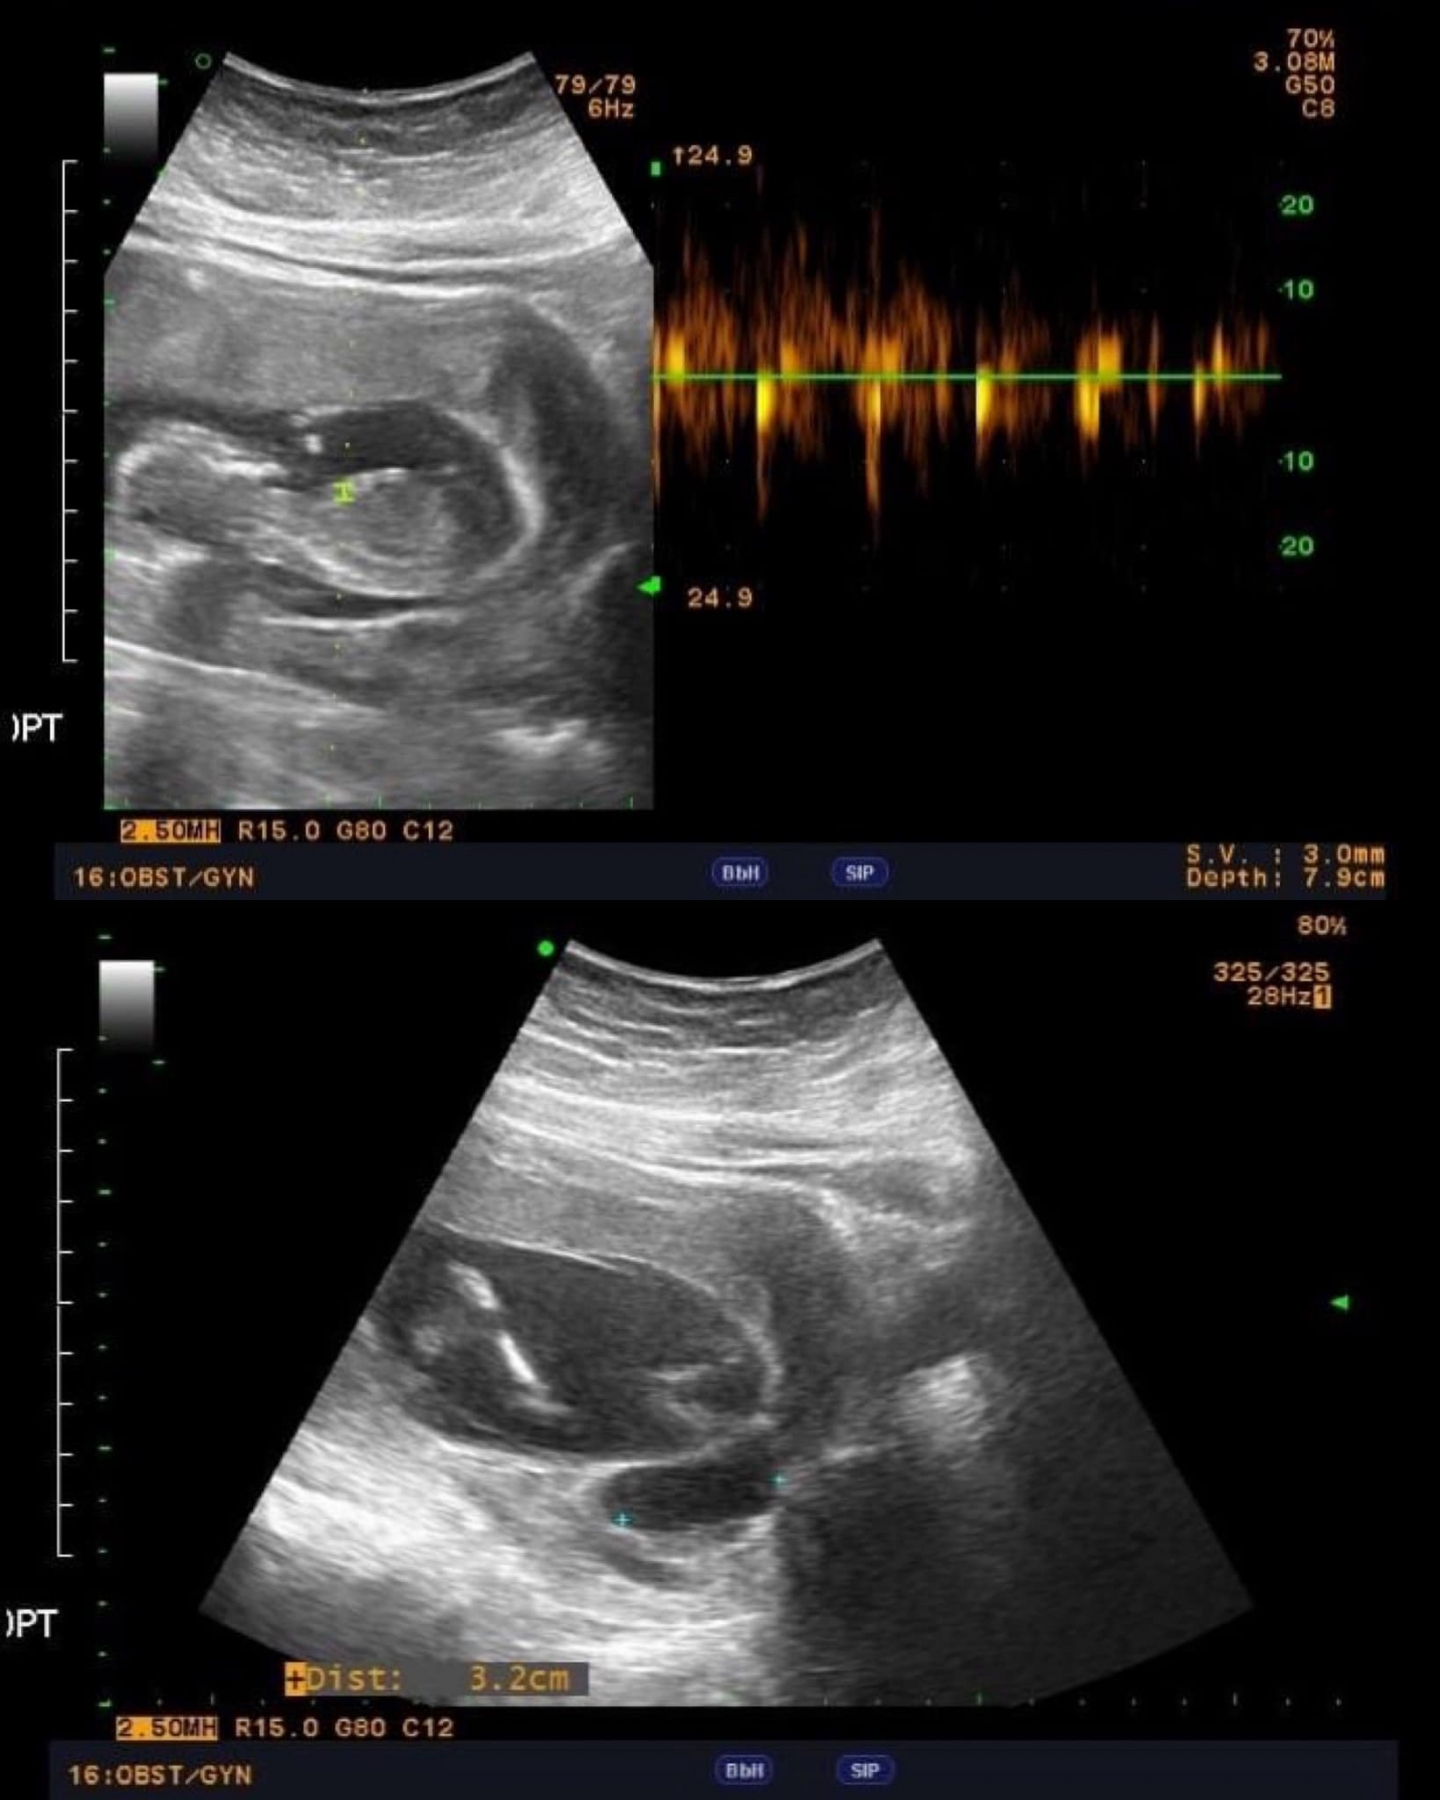

接下來的每一次產檢,都是他們最緊張的時刻。從最初的兩個胚胎,最終保留了一個健康的胎兒,雖然有些遺憾,但更多的是慶幸和感恩。

當胎兒的心跳聲在檢查室內回蕩時,他們的世界充滿了希望和喜悅。 她順利地迎來了她們的寶寶。